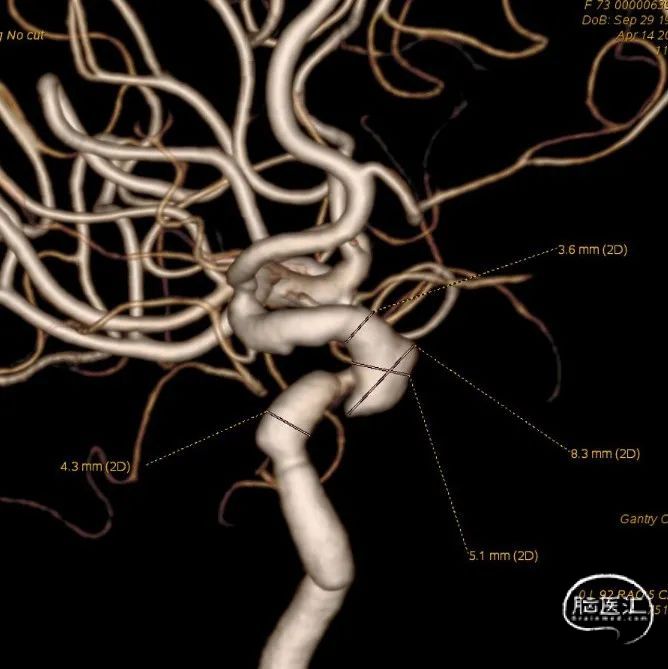

🔆 MRI+MRA检查:脑内散在少许腔隙性脑梗塞及小缺血灶。轻度脑白质疏松症;脑萎缩。脑动脉硬化伴双侧大脑后动脉、颈内动脉节段性狭窄。双侧颈内动脉C5段突起影,动脉瘤可能。

术前影像

右侧颈动脉造影

左侧颈动脉造影

左侧颈内动脉重建(左侧狭窄及扩张较右侧更甚)

1. 患者双侧颈内动脉多发瘤样扩张及狭窄,其中左侧为甚,破裂出血及出现缺血事件风险较高